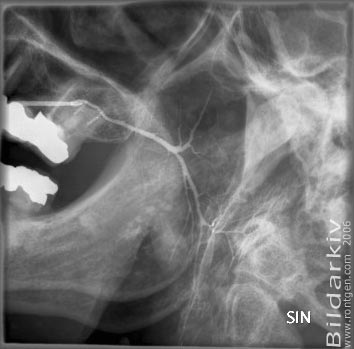

Spottkörtlar 1

Kontrastingjutning i öronspottkörtelns (glandula parotis) utförsgång.